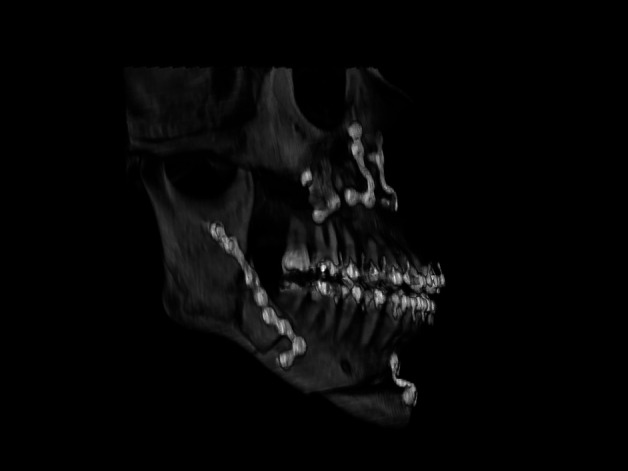

Material and methods: A retrospective analysis was conducted on 157 patients (314 osteotomies) over five years. Multi-slice helical CT scans, both pre- and post-operative, were examined to classify BS and identify potential risk factors. Anatomical variables included the presence of third molars, edentulism, prior fixation systems, mandibular ramus dimensions, lingula position, and alveolar crest height. Technical aspects of osteotomy execution were also assessed. Measurements were performed using Dolphin Imaging Software 11.95 after orienting the skull in the Natural Head Position.

Results: The incidence of BS was 3.2% (10 patients), with a slight left-side predominance (60%). Class A BS (distal fracture of the proximal segment) was the most common (60%). Anatomically, 83.3% of Class A cases had a more anteriorly positioned lingula and 66% presented a lower alveolar crest. Technically, 80% of BS cases showed deviations in osteotomy execution, with incomplete osteotomy at the basal level being the most frequent (60%).